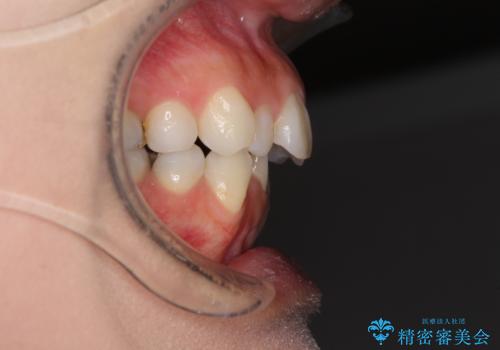

- 前歯のデコボコと矮小歯、更には痛みを感じる奥歯のむし歯を気にして来院された患者様です。

奥歯には根管治療が必要な歯があり、上顎側切歯は左右ともに矮小歯でした。